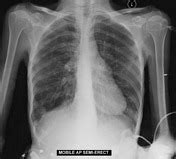

Right middle lobe consolidation - patchy | Image ...

Right middle lobe consolidation - patchy | Image ... from images.radiopaedia.org